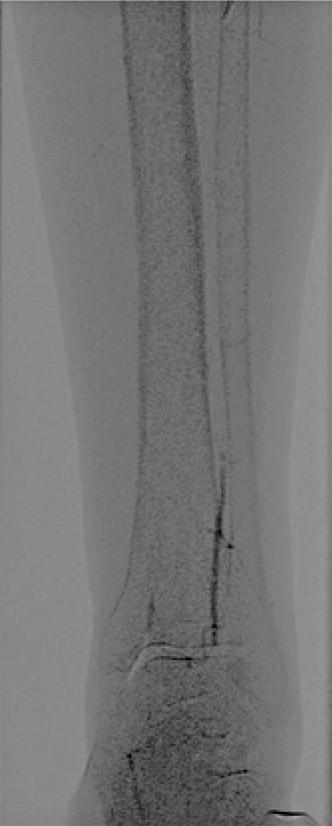

RESUMO O aneurisma gigante da artéria esplênica constitui condição rara, que representa risco de vida iminente para o paciente, necessitando, consequentemente, de correção cirúrgica urgente. Mulher de 61 anos, ex-fumante, hipertensa, com hipercolesterolêmica e multípara nos procurou por apresentar grande tumor no mesogástrio, achado de ultrassonografia abdominal. Apesar das dimensões do tumor, era assintomática. Angiotomografia e ressonância magnética de abdômen sugeriam tratar-se de aneurisma gigante de artéria esplênica com mais de 10cm de diâmetro, confirmado por angiografia. Foi submetida a […]